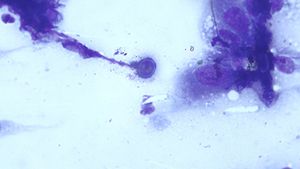

Below is a skin cytology from a 3-year-old male neutered Doberman pinscher with cutaneous lesions. Whats going on?

Published: September 26th 2019 | Updated: